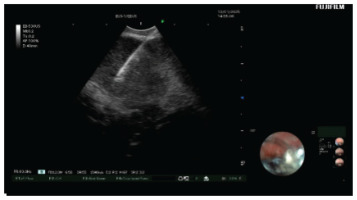

EBUS-TBNA was used to sample lymph node stations 4R, 7R, and 11R (Figure 3), and bronchoalveolar lavage (BAL) was performed in the right middle lobe. Histopathological analysis showed non-caseating granulomas with epithelioid histiocytes and surrounding lymphocytes (Figure 4), consistent with non-necrotic granulomatous inflammation. Rigorous laboratory and cytological examination of BAL suggested no other potential diagnosis.